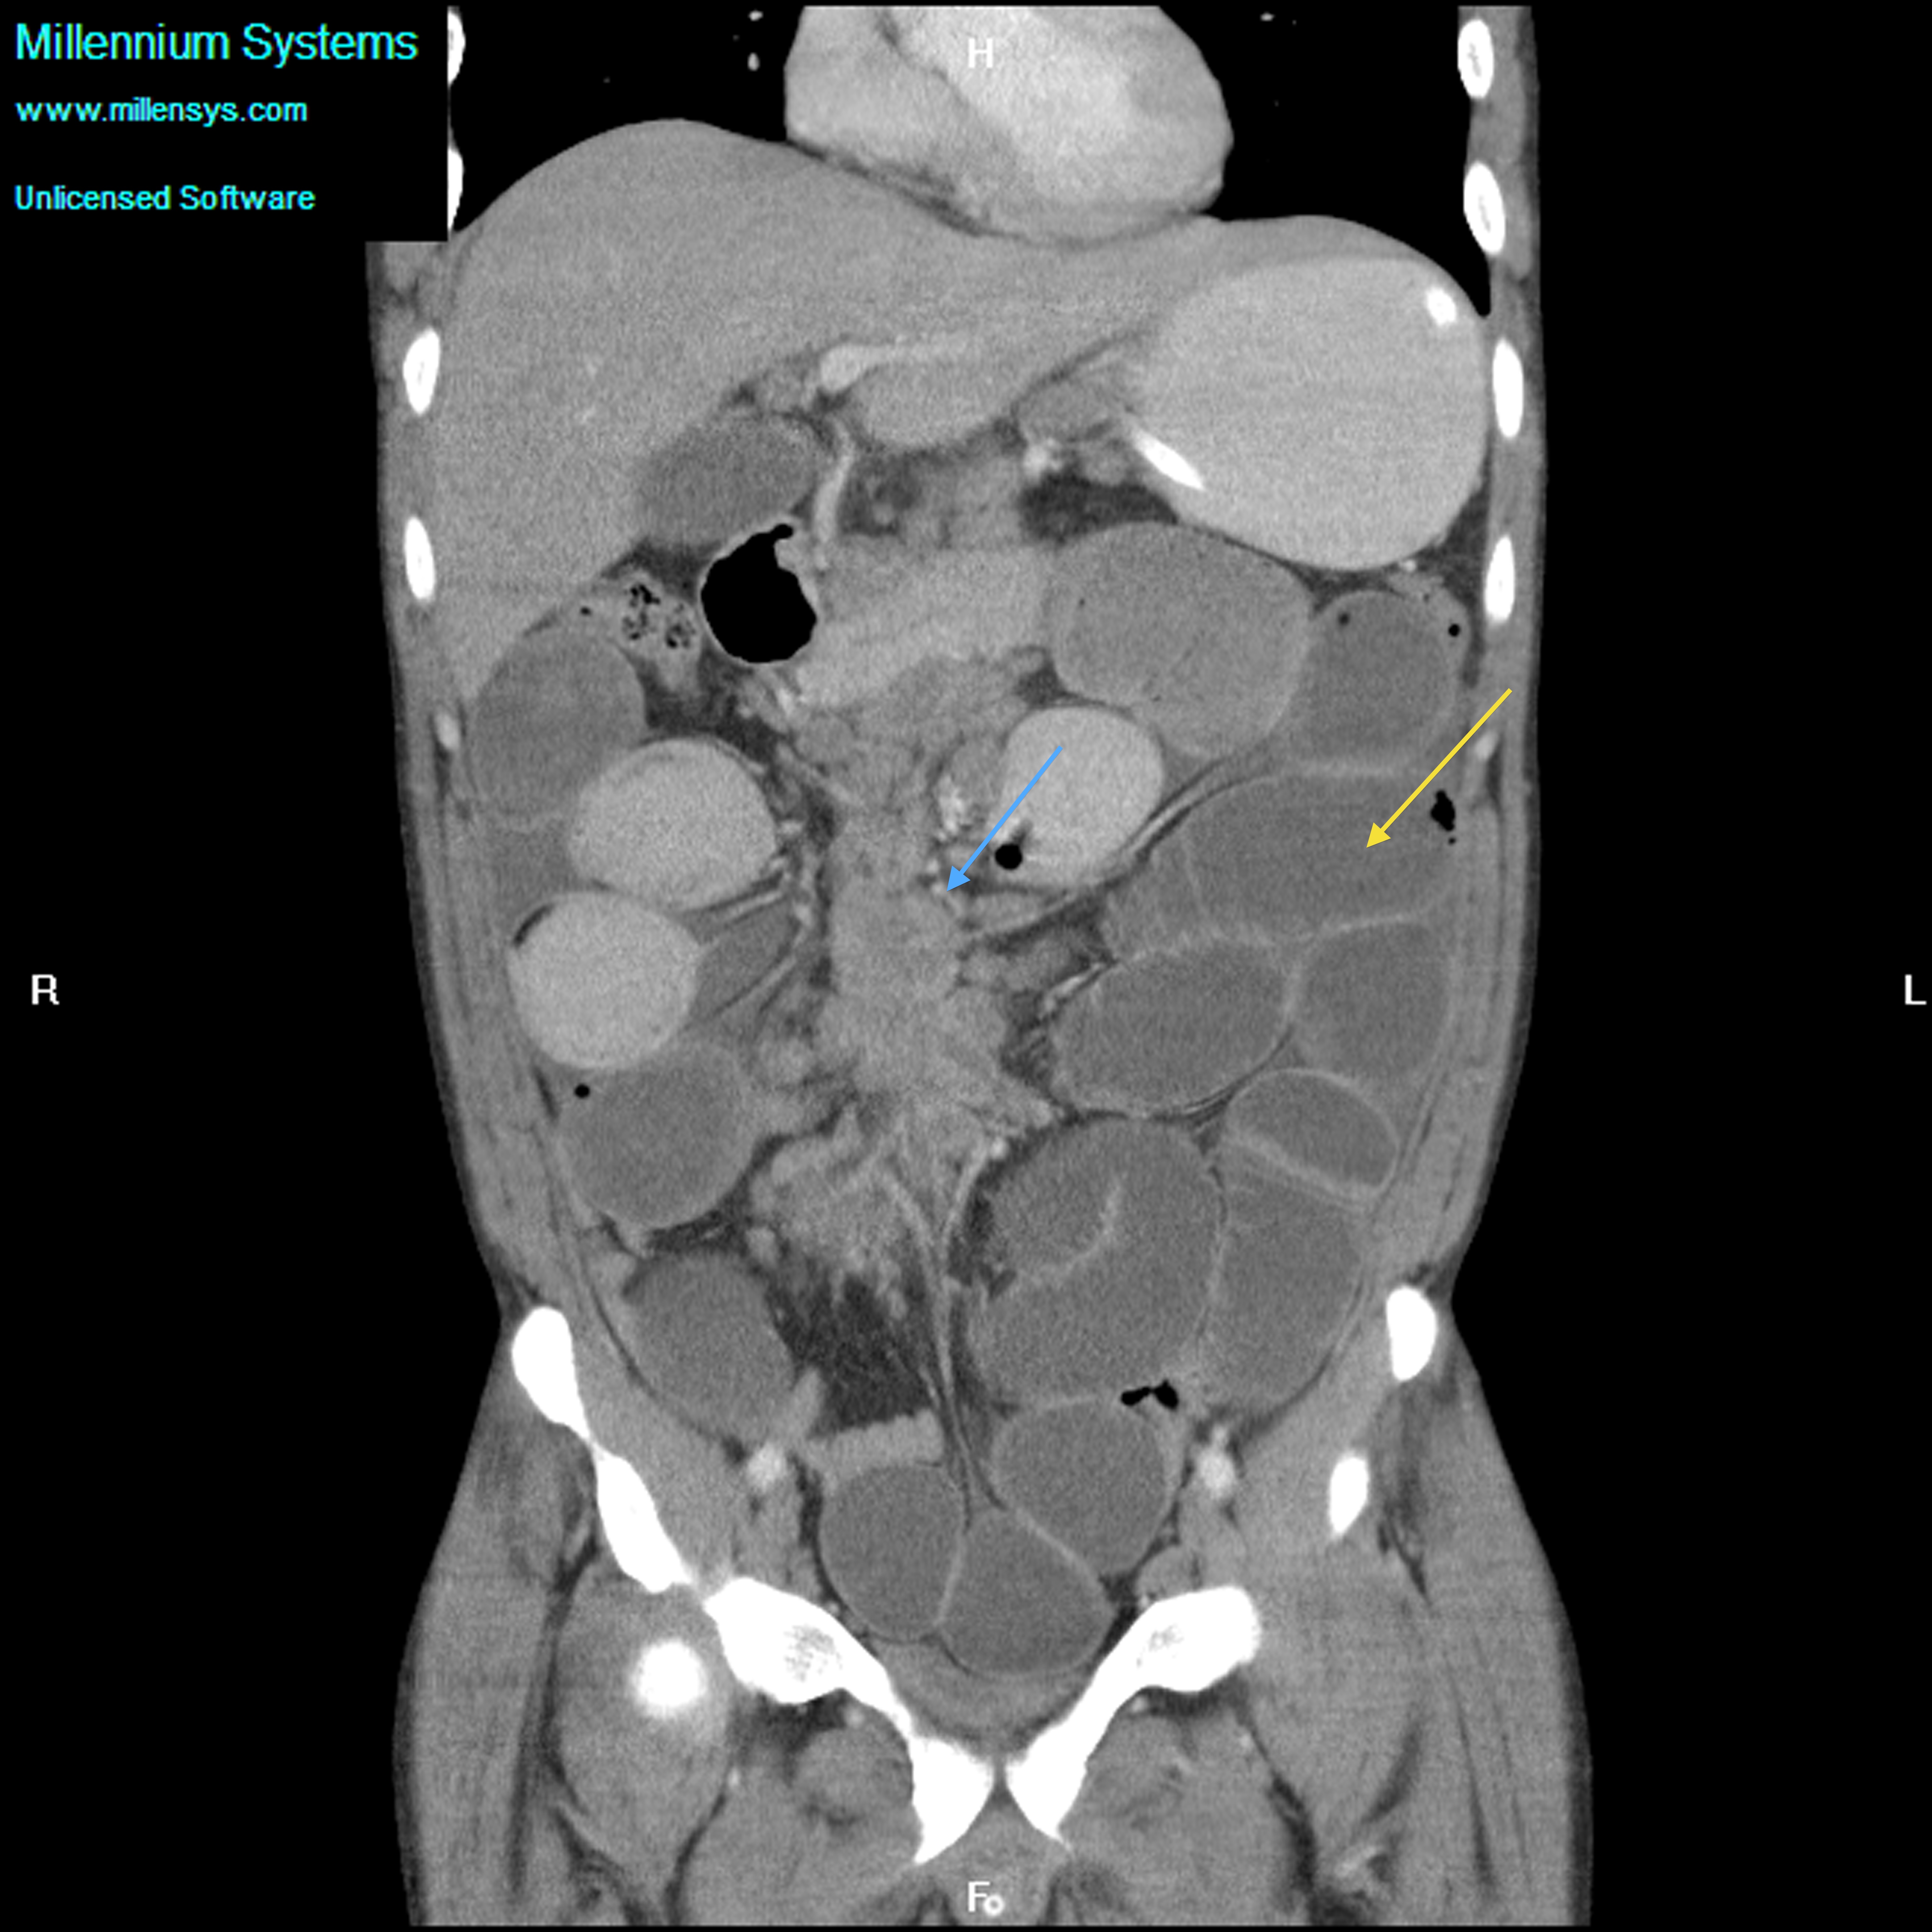

Small bowel obstruction is a common clinical presentation that presents a diagnostic conundrum. Over the last 2 decades, there has been a paradigm shift in the radiological investigation of small bowel obstruction (SBO) and in the indication for and timing of surgical intervention. Cross sectional imaging (predominantly computed tomography) has largely replaced the widespread use of radiographic small bowel follow-through studies as the imaging modality of choice for SBO. This article illustrates the current imaging modalities available for diagnosis of small bowel obstruction. (Full text available online at www.medpharm.tandfonline.com/ojfp) S Afr Fam Pract 2015; DOI: /10.1080/20786190.2014.977052